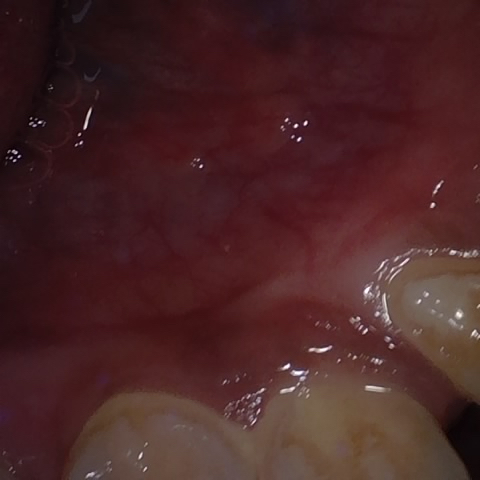

NHD38254

Annotated as "Good"

Original Image Rendering Image